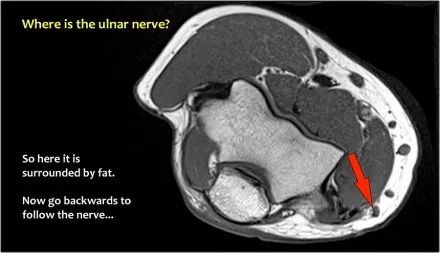

尺神经:在这里,我们看到了肘管内的尺神经。尺骨侧支带的后带形成隧道的底部,而支持带形成屋顶。

因此,当我们回到图像时,您会发现很难找到神经。任何这些皮下结构都可以是转位神经。一种方法是远端跟随结构,直到你发现远端的尺神经位于由脂肪包围的前臂近端的正常位置。然后当你向近端跟随它时,你会发现这是皮下移位。